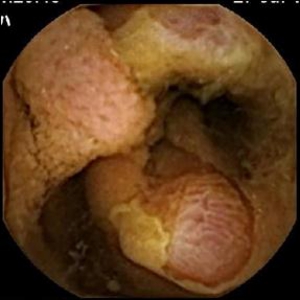

ESDとは内視鏡的に使用可能な高周波メスを使って、粘膜下層のレベルで病変を剥がし取る手技です。当科では、従来の内視鏡治療(EMR)では、一括切除が困難と思われる大腸腫瘍に対して積極的にESDを行っております。体を切開することなく組織も温存できるため、患者の身体的負担が少ない低侵襲医療のひとつです。

《大腸ESDの実際》